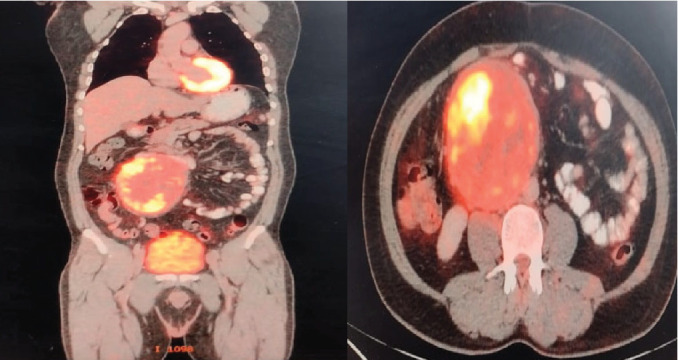

Background: Primary retroperitoneal seminoma is an exceedingly rare type of germ cell tumor, accounting for less than 5% of all such tumors. These tumors are typically large at presentation due to their slow growth and the nonspecific nature of symptoms, which often leads to delayed diagnosis. Case Presentation: A 40-year-old male presented with intermittent abdominal pain and a palpable lump in the right paraumbilical region. Ultrasonography revealed a large retroperitoneal mass. Fine needle aspiration cytology confirmed the diagnosis of poorly differentiated malignant tumor, for which he was evaluated with CT-angiogram of the abdomen and FDG PET-CT scans, which showed a large retroperitoneal mass. The patient, then, had a surgical resection of the mass, with postoperative histopathological and immunohistochemical diagnosis of primary retroperitoneal seminoma, and then underwent three cycles of BEP chemotherapy. Scrotal ultrasonography showed no testicular abnormalities, obviating the need for orchiectomy. FDG PET showed a complete response following treatment completion. Postoperative management included routine monitoring of tumor markers and follow-up imaging, which showed a complete response. Conclusion: This case highlights the diagnostic and therapeutic challenges of primary retroperitoneal seminoma. A multidisciplinary approach, including accurate histopathological diagnosis and a combination of chemotherapy and surgery, is essential for optimal management. Early diagnosis and tailored treatment strategies significantly improve patient outcomes.